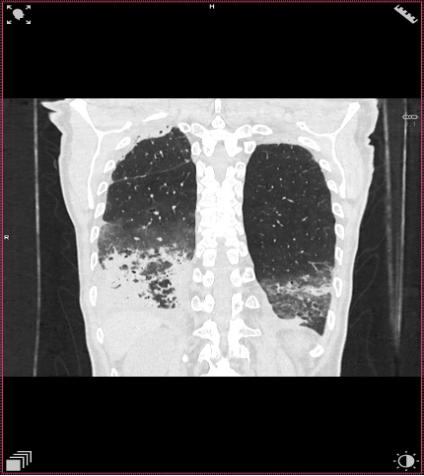

TC ventana pulmón